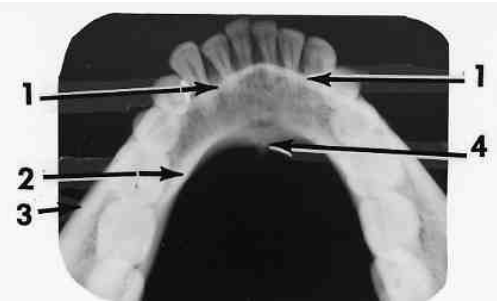

9. What is the anatomical structure indicated by arrow in this radiograph?

10. Which option indicated by arrow number 4 ?